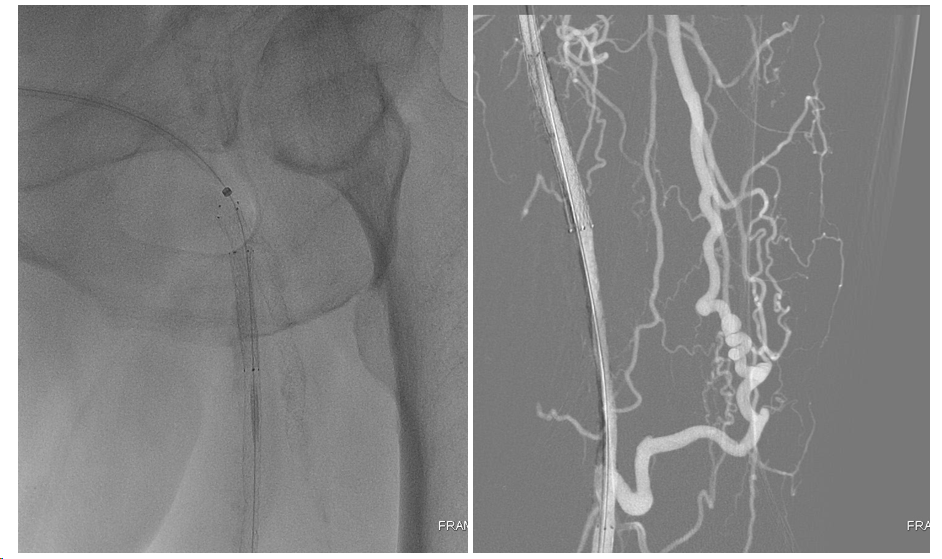

患者平卧位,局麻后顺行穿刺左侧人工血管植入6F 45cm鞘,造影提示人工血管吻合口远端股总动脉短段闭塞、股浅动脉长段闭塞、股深动脉开口闭塞(图6-7)。

(图6)术前造影,可见人工血管吻合口远端股总动脉、股深动脉开口、股浅动脉闭塞,腘动脉、膝下胫前、胫后动脉通畅,足背-底弓完整。

(图7)股总动脉分叉区造影

首先选择治疗股深动脉病变,至少保证建立股总-股深-膝关节动脉网连续血流以恢复患肢血供。为了尽可能延长股深动脉的通畅时间,在4mm 、5mm Saber球囊预扩后,我们选择使用Resolute Integrity 冠脉药物涂层支架4*30mm覆盖股深动脉病变。接着,我们计划采用药物涂层球囊扩张股总-股浅动脉病变,在分别使用Orchid药物涂层球囊5.5*300mm、5.5*120mm扩张股浅动脉后,我们通过复查造影发现股浅动脉开口存在限流性夹层,为了确保金属裸支架释放过程中不会因为“前跳”现象而过度“出头”,我们选择了兼具极佳径向支撑力和释放精度的Smart Flex支架(5*150mm、5*120mm各一枚),利用Kissing Stent技术重建股动脉分叉,复查造影,股总-股浅及股总-股深均恢复连续血流(图11),术后3天患者顺利出院。

(图11)股深动脉DES+股浅动脉Smart Flex,利用Kissing Stent技术重建股动脉分叉